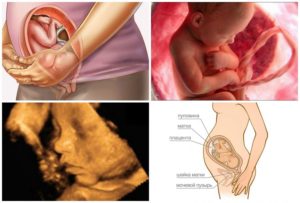

Скорее всего, вы уже прошли последнее ультразвуковое исследование, во время которого была окончательно установлена предполагаемая дата родов. Но бывает, что УЗИ назначают и на 37 неделе беременности для уточнения ряда моментов.

Один из главных вопросов: как расположился малыш перед выходом «на волю».

Большинство деток устремляется головкой вниз, поскольку эта поза является наиболее физиологичной: именно так рожаться будет легче всего, да и матка имеет такую форму, что перевернутый вниз головой ребеночек повторяет ее очертание, что очень удобно в условиях катастрофической нехватки места. Тем не менее, некоторые ребятки садятся на попу или укладываются поперек. Ягодичное предлежание на сегодняшний день не является абсолютным показанием к кесареву сечению, но оперативное родоразрешение может быть назначено с учетом отягощающих факторов.

Специалист во время ультразвуковой диагностики на 37 неделе внимательно осмотрит ребеночка и степень его развития, зафиксирует основные параметры, сердцебиение, оценит состояние и количество околоплодных вод, состояние матки и шейки, пуповины, степень зрелости плаценты. Скорее всего, будет проведена также допплерография для оценки маточно-плацентарного кровотока.

Снимки УЗИ на 37 неделе